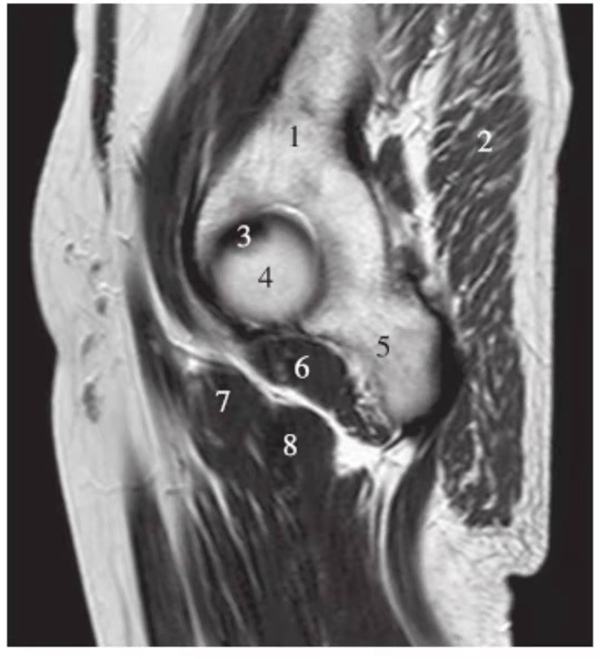

正常髋关节经股骨头外缘层面T1WI像

1.臀中肌;2.臀大肌;3.臀小肌;4.关节囊及髂股韧带;5.髂腰肌;6.股骨颈;7.骨岛;8.股直肌;9.股中间肌

冠状位

正常髋关节经股骨头前缘层面T1WI像

1.股骨头;2.耻骨;3.髂骨;4.髂腰肌;5.内收肌群;6.臀小肌;7.臀中肌;8.关节囊及髂股韧带